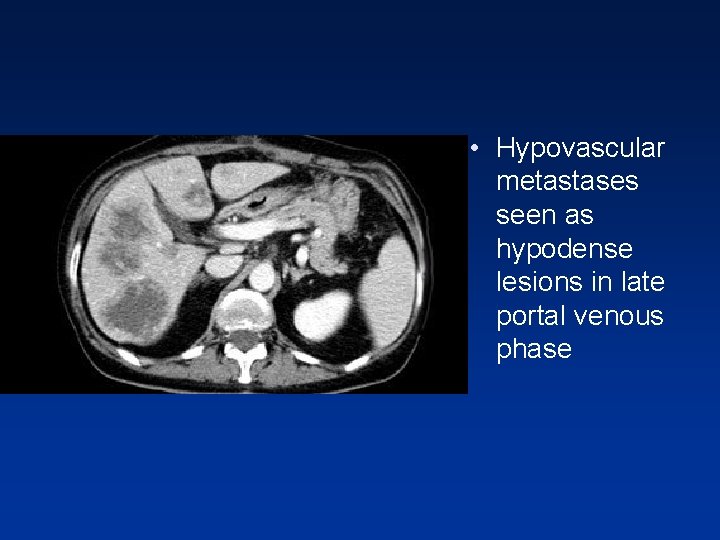

• Hypovascular metastases seen as hypodense lesions in late portal venous phase